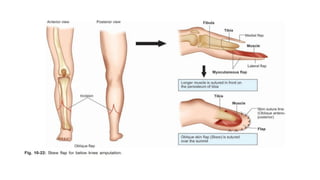

BELOW-KNEE (TRANSTIBIAL) AMPUTATION

• The long posterior flap - length 1.5 times the diameter of the leg.

• The anterior flap is cut down to bone at the level of bone division.

• Elevation of the anterior flap of skin and muscle off the underlying bone is kept to a

minimum, and 1 cm is adequate.

• The tibia is then divided and bevelled anteriorly.

• The fibula is divided 1 cm more proximally.

• The posterior flap should retain deep fascia and some underlying muscle throughout

its length in order to safeguard skin perfusion. However, the muscle bulk must be

reduced to obtain a tapered stump.

• The posterior muscles are divided

obliquely so that virtually all of the

deep muscle is removed, and distally,

only a thin remnant of the superficial

gastrocnemius remains.

• Arteries are ligated as they are

encountered and nerves divided so that

they can retract.

• The muscles of the flaps are apposed

over the bone with sutures through deep

fascia, and the skin is closed over

suction drainage.